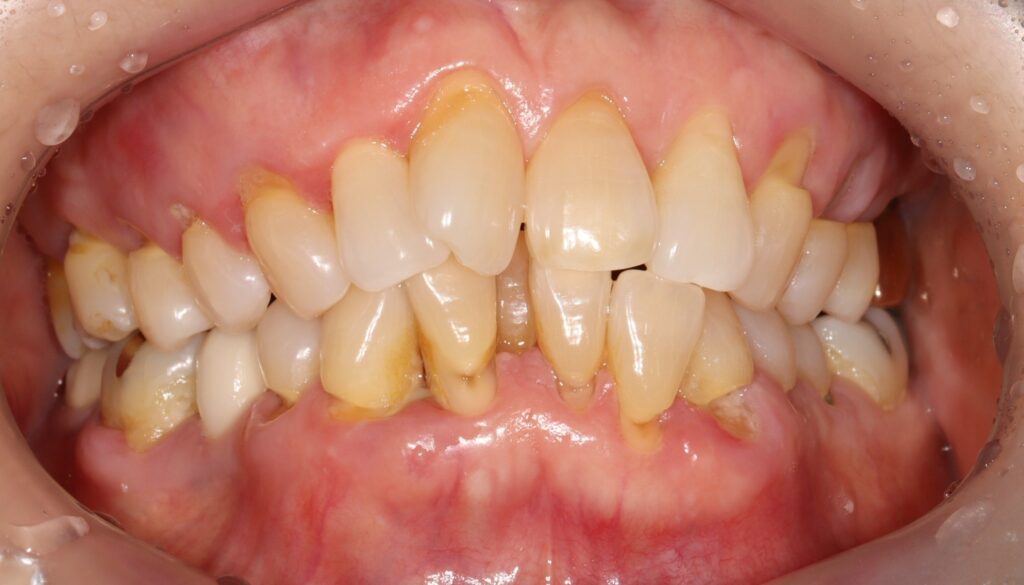

환자분께서는 70대 여성분으로

치아의 신경이 노출될 정도로 심하게

치경부가 패여 있는 상황이었는데요.

치경부마모증으로 인해

이가 시린이유는 상아질이 노출되었기

때문으로 상아질에는 미세한 관이 있어서

외부 자극에 매우 예민합니다.

치경부가 마모되면서 치아 조각이 떨어져 나가고

상아질이 노출되어 찬물, 바람 등에도

치아 시림을 느끼게 되는 것인데요.

위쪽 작은 어금니 두개는 신경관이 보일 정도였지만

현재 증상이 없다고 하셔서 치수 복조 후 레진,

아래 송곳니는 신경치료 후 레진으로

수복할 수 있도록 계획하였습니다.